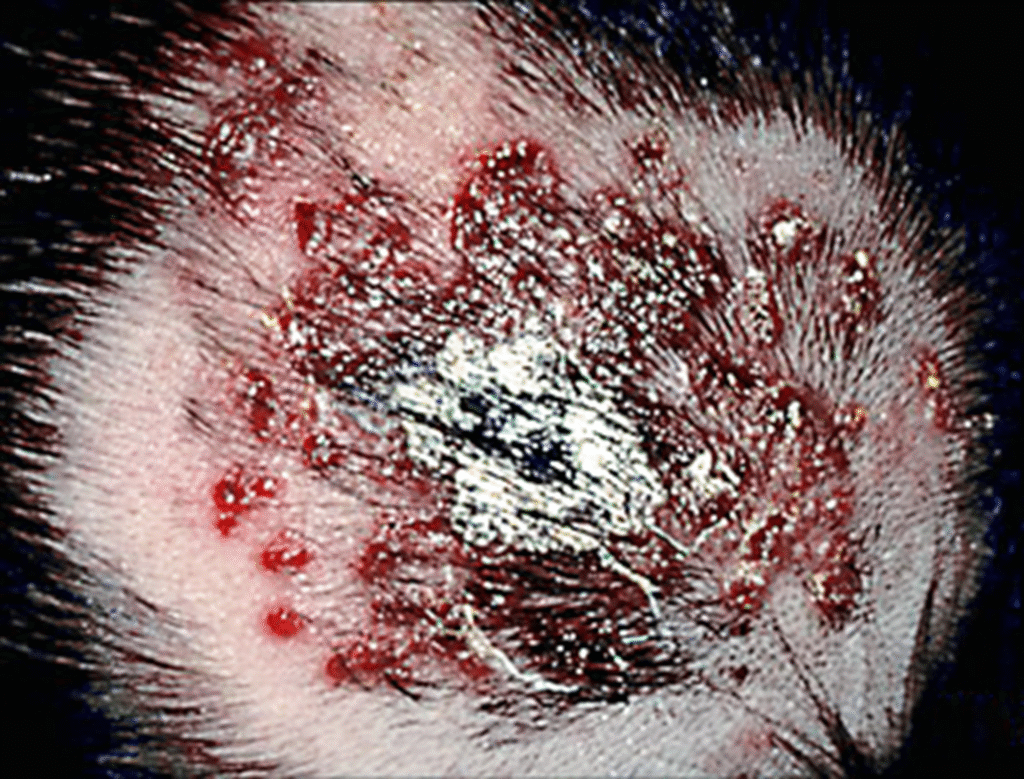

• ვეზიკულური გამონაყარი ახალშობილებში, რომლებსაც აქვთ ცნს-ის ჰერპეს სიმპლექსის ვირუსი (HSV) (სურათი 1A-C).

(სურათი 1A-C).

ახალშობილის თავის კანის დაზიანება, რომელსაც აღენიშნებოდათ კანის, თვალის და პირის ღრუს ახალშობილთა ჰერპესული ვირუსული ინფექცია, რომელიც დაკავშირებული იყო ნაყოფის თავის კანთან. გრამის წესით შეღებილი ნაცხი და ბაქტერიული კულტურები უარყოფითი იყო და დაზიანებები არ რეაგირებდა ადგილობრივ და სისტემურ ანტიბიოტიკებზე. ვირუსულ კულტურებში გაიზარდა მე-2 ტიპის ჰერპესული ვირუსი და დაზიანებებმა მოახდინა რეაგირება ინტრავენურ აციკლოვირზე.